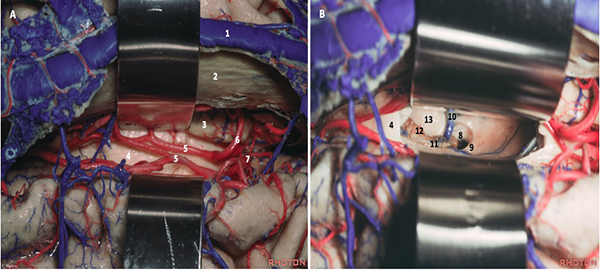

Durotomía arciforme con base al SSS, respetando componentes venosos que suelen encontrarse. Aunque estas estructuras de drenaje a lo largo del tercio anterior del SSS se consideran seguras de ligar, el riesgo de infarto venoso está descripto de forma predominante cuando son voluminosas y no hay venas suplementarias que drenen el determinado sector. En consecuencia, su manipulación y sacrificio deben mantenerse al mínimo. Se realizó drenaje del líquido cefalorraquídeo (LCR) mediante punción lumbar aproximadamente 12 cc para descomprimir el parénquima y favorecer la separación. Los retractores fijos se tratan de evitar mediante el uso de retracción dinámica, intermitente e inducida por la gravedad (rotación de la cabeza de forma que el seno sagital se posicione paralelo al suelo, o colocar al paciente en decúbito lateral). Una vez identificado el lugar apropiado para acceder a la fisura interhemisférica, comienza su disección con técnica microquirúrgica y utilizando microscopio (Leica M525 OH4), se procede a la apertura de la aracnoides con microtijera en sentido longitudinal, debiendo reconocer la circunvolución frontal superior lateralmente y el borde libre de la hoz del cerebro, inmediatamente después encontrándose la circunvolución del cíngulo. La neuronavegación permite localizar sin dificultad al cuerpo calloso, disminuyendo el tiempo quirúrgico. Puede a su vez distinguirse por el color blanco nacarado, avascular y con las arterias pericallosas sobre su cara superior, las cuales se disecan por la línea media exponiéndolo (Figura 4A). En ocasiones, éstas pueden desplazarse hacia lateral o adherirse, lo que dificulta su separación con riesgo de lesionarlas.9 La callosotomía se realiza en el tercio anterior, en sentido anteroposterior con coagulación bipolar y tijera microquirúrgica, no debiendo exceder de 20 mm, lo cual proporciona adecuada visualización del foramen de Monro, las venas cerebrales internas, coroideas y talamoestriadas.10 11 12 Esta apertura limitada generalmente no implica secuelas neuropsicológicas postoperatorias (Figura 4B-5).

Figura 4. Anatomía quirúrgica de la cisura interhemisférica (A) y posterior a callosotomía (B): seno sagital superior (1); hoz del cerebro (2); circunvolución del cíngulo (3); cuerpo calloso (4); arteria pericallosa (5) y callosomarginal (6); arteria cerebral anterior (7); foramen de Monro (8); pilar del fórnix (9); vena talamoestriada (10); vena coroidea (11); plexo coroideo (12); tálamo (13). Adaptado de: The Rhoton Collection®33

Figura 5. Imagen transoperatoria: realizada la callosotomía se aprecia lesión quística* descrita.